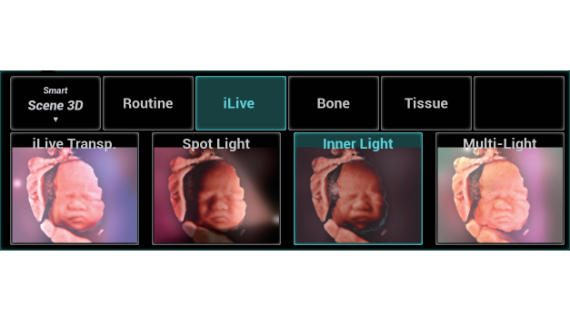

Gambar Klinis